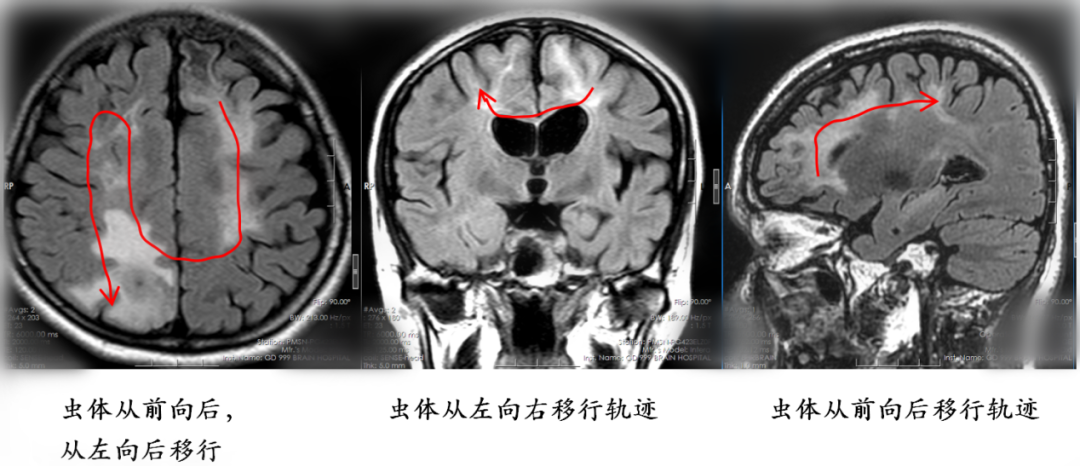

根据复查影像,该院神经外八科二区王艮波主治医师发现虫体已转移到患者的右侧顶叶非功能区,“随访近4年,手术时机终于到了!”4月23日,神经外八科二区团队为患者行开颅手术,不仅顺利“生擒”一条20余厘米的虫子,还将“虫窝”(炎性肉芽肿)一并切除。